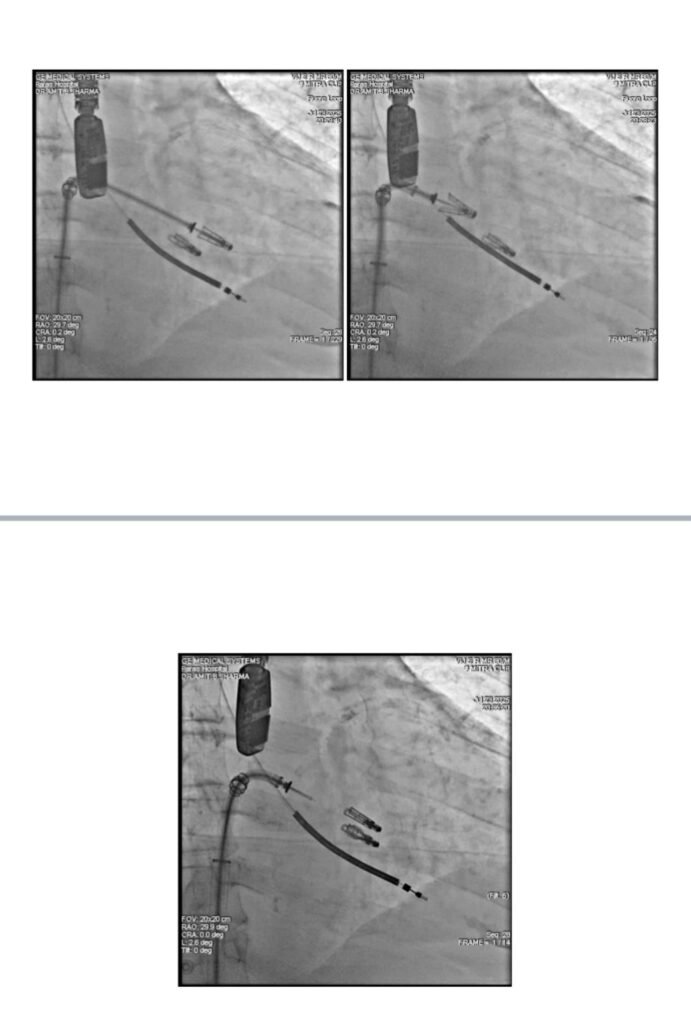

A multidisciplinary team led by Dr. Amit Bhushan, Director & Unit Head – Cardiology, Paras Health Gurugram, performed a rare, high‑risk dual intervention using MitraClip (TEER) to repair the severely leaking mitral valve and restore circulation.

“This was one of the most challenging cases we have managed. A single intervention alone could not have saved him. We deployed a second MitraClip, during which the patient went into shock and required CPR. After multiple episodes of instability, he was revived. The MitraClip repaired the leaking valve, restored forward blood flow, and stabilised the heart enough to support recovery. This coordinated, stepwise approach was the only viable path when every other option had been exhausted.”

TEER (Transcatheter Edge‑to‑Edge Repair) is a minimally invasive valve‑repair procedure performed through a vein in the leg. A small clip is attached to the leaking mitral valve to prevent backward blood flow, improving heart rhythm and pumping efficiency. It is often the only option for patients too high‑risk for open‑heart surgery.

The complex intervention involved 14 specialists, including interventional and non‑invasive cardiologists, cardiac anaesthesia, intensivists, cath‑lab teams, paramedical staff, and technical experts guiding the MitraClip under 3D TEE and fluoroscopy.